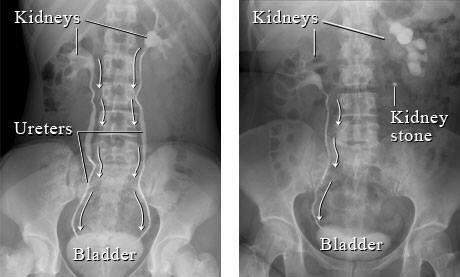

Diagnosis

Diagnosis of stone is mainly radiological with ultrasound and x-rays. Laboratory Tests are performed to look for urine infection and function of the kidneys:

• • X Ray abdomen and pelvis

• • Ultrasound KUB

• • IVU (Intravenous Urography)

• • CT Urography